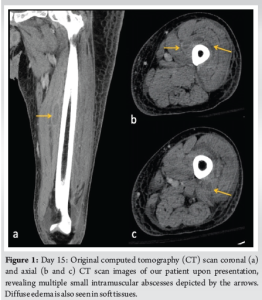

Day 15: He returned to the ED endorsing progressive pain, swelling, and weakness. The patient was AO×3, afebrile, toxic appearing, and tachycardic to 118 beats/min. Inspection of the left leg revealed faint erythema with warmth, with tenderness to palpation over the anterior mid-thigh to the mid-leg. The left thigh and leg compartments were soft and compressible. A small effusion was detected on examination of the left knee. The patient had limited range of motion to the left knee but was neurovascularly intact. The general surgery team was consulted for concern of a soft-tissue infection. Lab results revealed an elevated white blood cell count (21.6 K/mcL), erythrocyte sedimentation rate (90 mm/h), C-reactive protein (274 mg/L), and serum glucose (301 mg/dL). The patient had decreased serum sodium levels (123 mEq/L) and Hb (11.1 g/dL). The serum creatinine was within the normal range (0.96 mg/dL). Laboratory Risk Indicator for NF (LRINEC) score was 9, which was considered high risk for a developing NF [11-13]. Blood cultures drawn in the ED revealed MSSA bacteremia. Computed tomography (CT) of the left lower extremity revealed small pockets of peripheral enhancing fluid collections within the vastus medialis, intermedius, and lateralis consistent with multiple abscesses. The patient’s imaging also exhibited diffuse soft-tissue thickening and fat stranding consistent with cellulitis (Fig. 1).